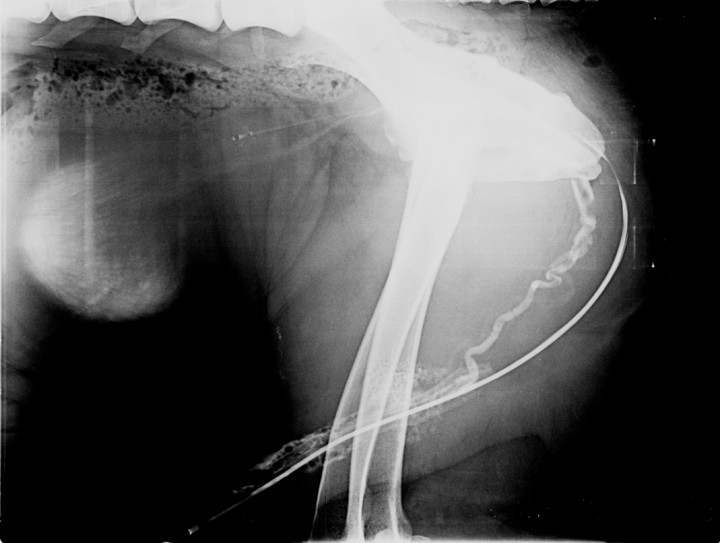

En la exploración física el paciente mostró estado y constantes normales, exceptuando dolor en la zona abdominal caudal y distensión vesical a la palpación. Se hizo una radiografía de abdomen simple, que confirma la dilatación vesical. A continuación, se realizó una uretrografía retrógrada (Fig. 1).

<p>Uretrografía retrógrada de un San Bernardo de 2 años que se presenta con estranguria, hematuria y disuria.</p>

Uretrografía retrógrada de un San Bernardo de 2 años que se presenta con estranguria, hematuria y disuria.

En la imagen obtenida tras realizar la uretrografía se identifica el recorrido de la uretra por la presencia de la sonda uretral y la columna de contraste positivo, con morfología normal en sus segmentos perineal e intrapelviano. Craneal a la uretra perineal, se observa una segunda estructura tubular, de recorrido sinuoso, que se extiende desde el área intrapelviana hasta el pene. Esta estructura es compatible, por morfología y localización, con la vena dorsal del pene, que desemboca en la vena pudenda interna a nivel de la entrada de la pelvis. Alrededor del segmento peneano de la uretra se aprecia un patrón de captación de contraste de aspecto moteado, causado por el llenado de los cuerpos cavernosos del pene (Fig. 2).